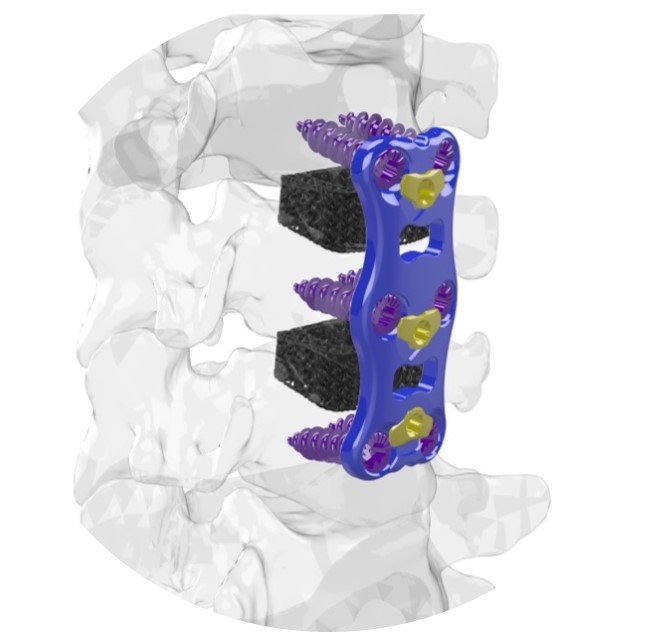

Key features of the Ti-Largo 3D Printed Cervical Cage include:

• Patient-Centric Design: Each Ti-Largo cervical cage is designed to meet the unique anatomical needs of the patient. This personalized approach ensures a precise fit and optimized spinal stability.

• Enhanced Biocompatibility: The Ti-Largo cage is 3D printed from a high-grade titanium alloy known for its excellent biocompatibility, corrosion resistance, and strength. This material minimizes the risk of adverse reactions and offers long-term durability.

• Minimally Invasive Surgery: The Ti-Largo implant is designed for minimally invasive cervical spine surgery, reducing tissue disruption, post-operative pain, and recovery time for patients.

• Optimized Osseointegration: The porous structure of the Ti-Largo cage facilitates bone ingrowth, promoting fusion and long-term stability.

The Ti-Largo 3D Printed Cervical Cage couples with FloSpine’s Panama Anterior Cervical Plate, which received FDA clearance in 2021. This combination provides surgeons with a comprehensive solution for anterior cervical spine surgery, ensuring stability, alignment, and long-term fusion.